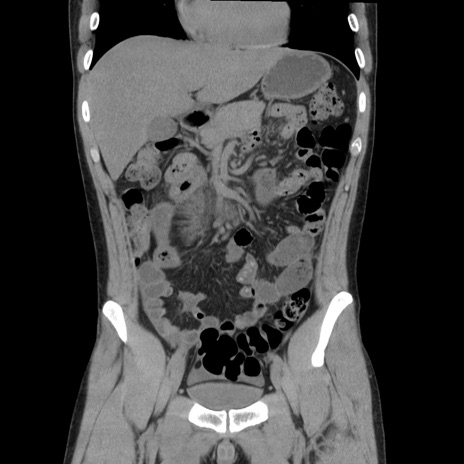

症例36(冠状断像)

【症例】20歳代 男性

【主訴】心窩部痛

【現病歴】今朝より上腹部痛あり。一旦軽快していたが再度出現したため救急要請。昨日夕に白身の魚を含む刺身を食べた。

【身体所見】BP 136/89mmHg、HR 74/min、BT 37.0℃、腹部:膨満、軟、心窩部に圧痛あり。反跳痛なし、筋性防御なし、腸雑音やや亢進あり。

【データ】WBC 17700、CRP 0.48